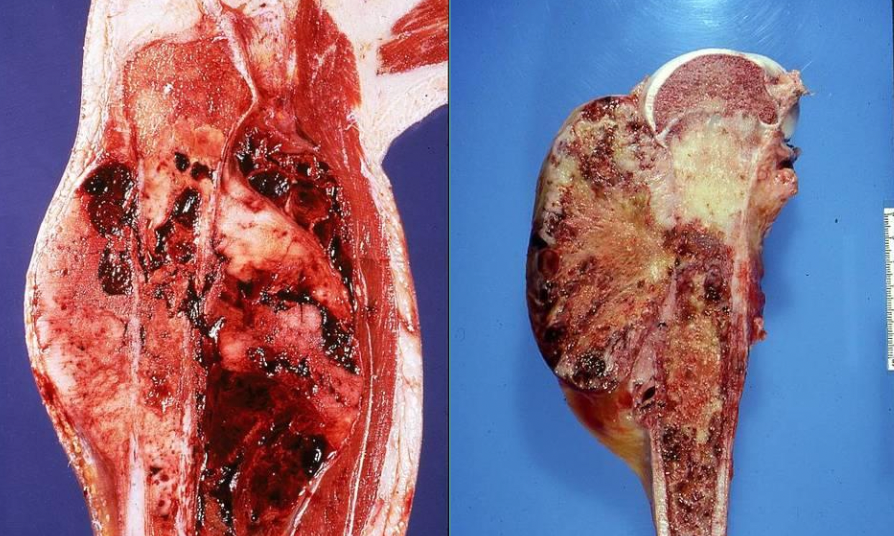

Chondrosarcoma, low grade on left, high grade on right